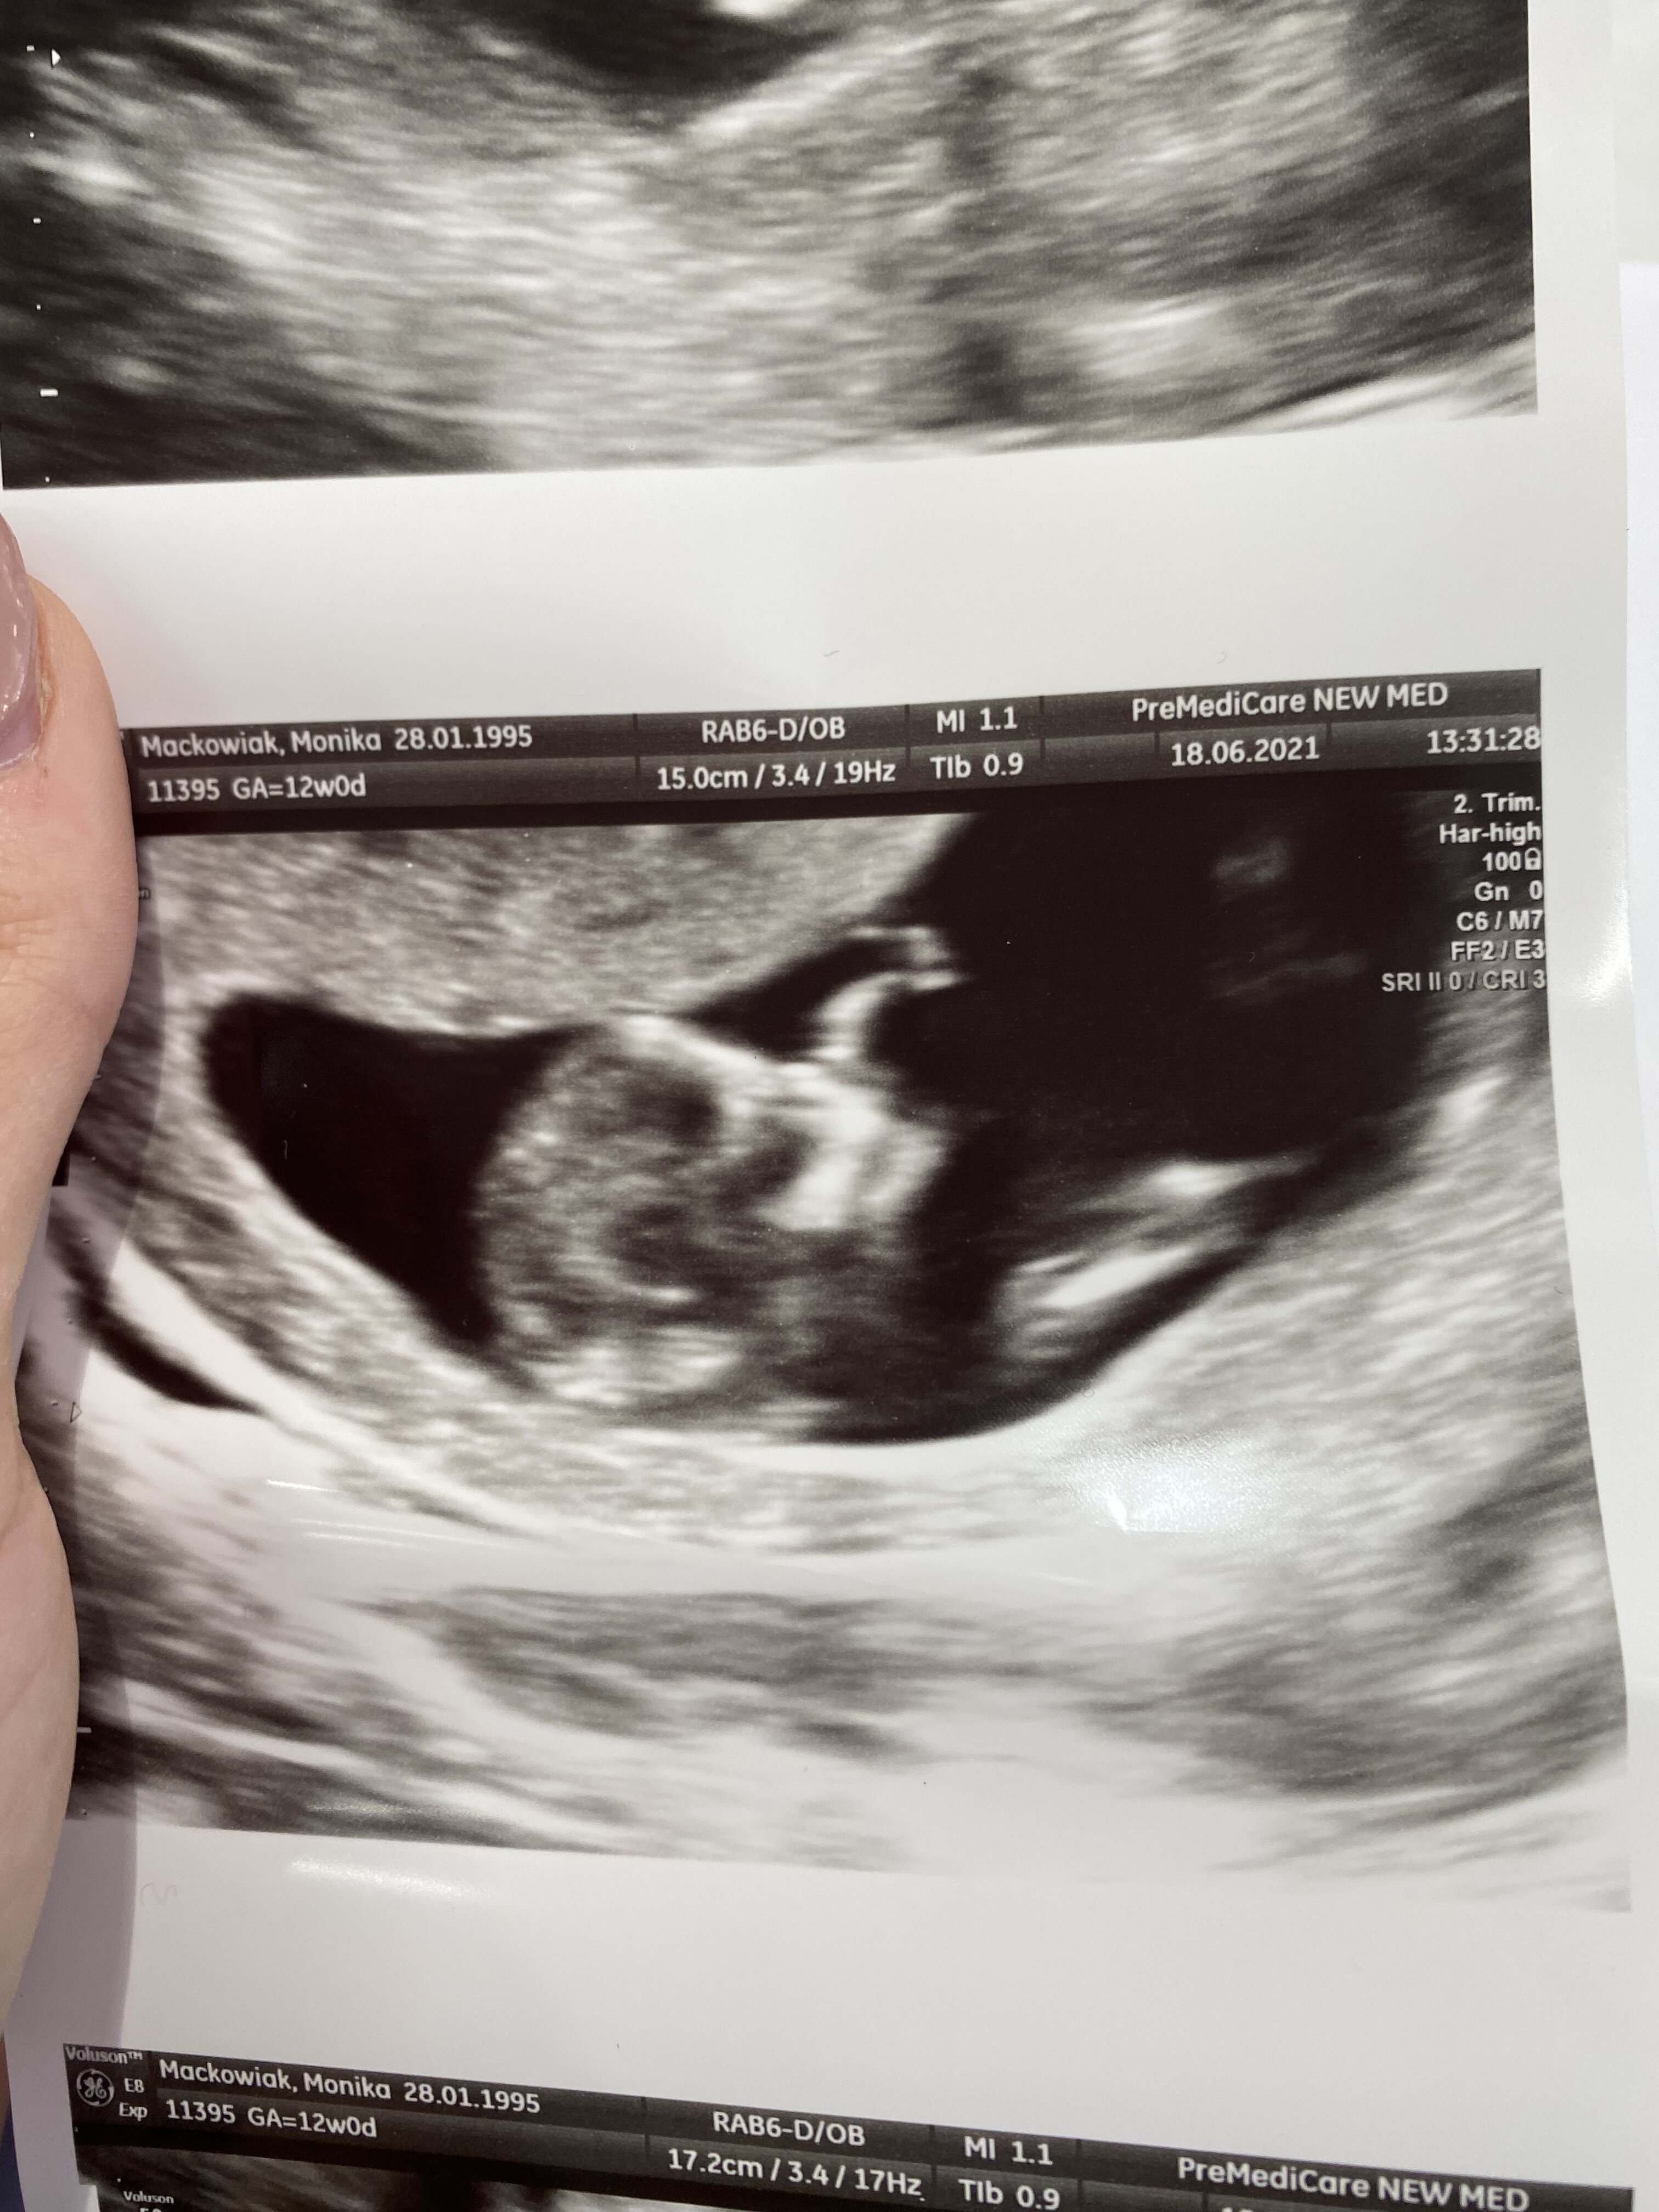

1 wizyta 4.06 5t5d z om potwierdzona ciaza (widoczny pęcherzyk ciążowy, kropeczka cialka żółtego), 11.06 6t5d z om pierwsze usg ze zdjęciem - ciałko żółte 3,78mm, pęcherzyk ciążowy 9,87mm, zawiazki zarodka i brak serca, trzecia wizyta dzisiaj 7t5d z om - bez pomiarów bo to u doktor prowadzącej - jest spory pierścień i zarodek ale brak serca. Kolejne USG za tydzien z pomiarami. Zaczynam tracić nadzieje, cykle co prawda 30-31 dni ale tak liczyłam na to, ze dzisiaj już coś będzie pulsowało na usg